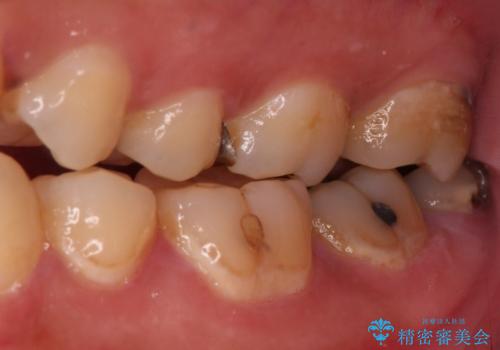

- 奥歯の銀歯がすぐに外れてしまうとのことで来院された患者様です。

何度か銀歯の詰め物を作ったものの、しばらくすると外れてしまうそうで、来院時には銀歯のない状態でした。

咬み合わせをみると、奥歯に負担がかかりやすいことが分かったので、適合がよく、硬さが歯と近いPGAインレー(白金加金合金インレー)にて修復治療を行うこととしました。